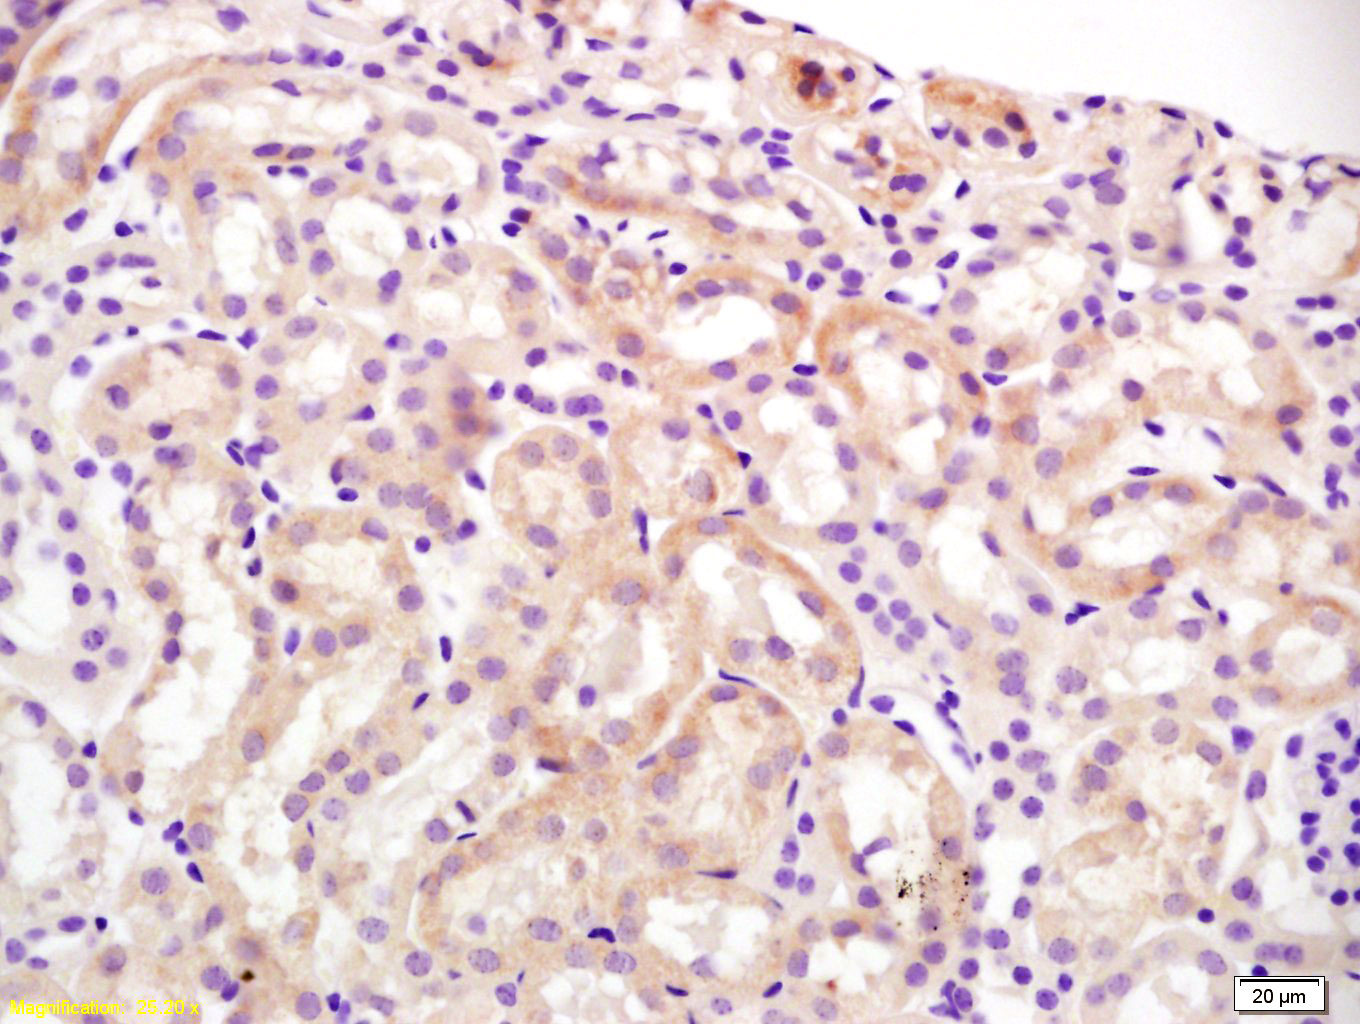

Formalin-fixed, paraffin-embedded mouse kidney for Slco1a1 Antibody was diluted at 1:200 dilution in immunohistochemical analysis.